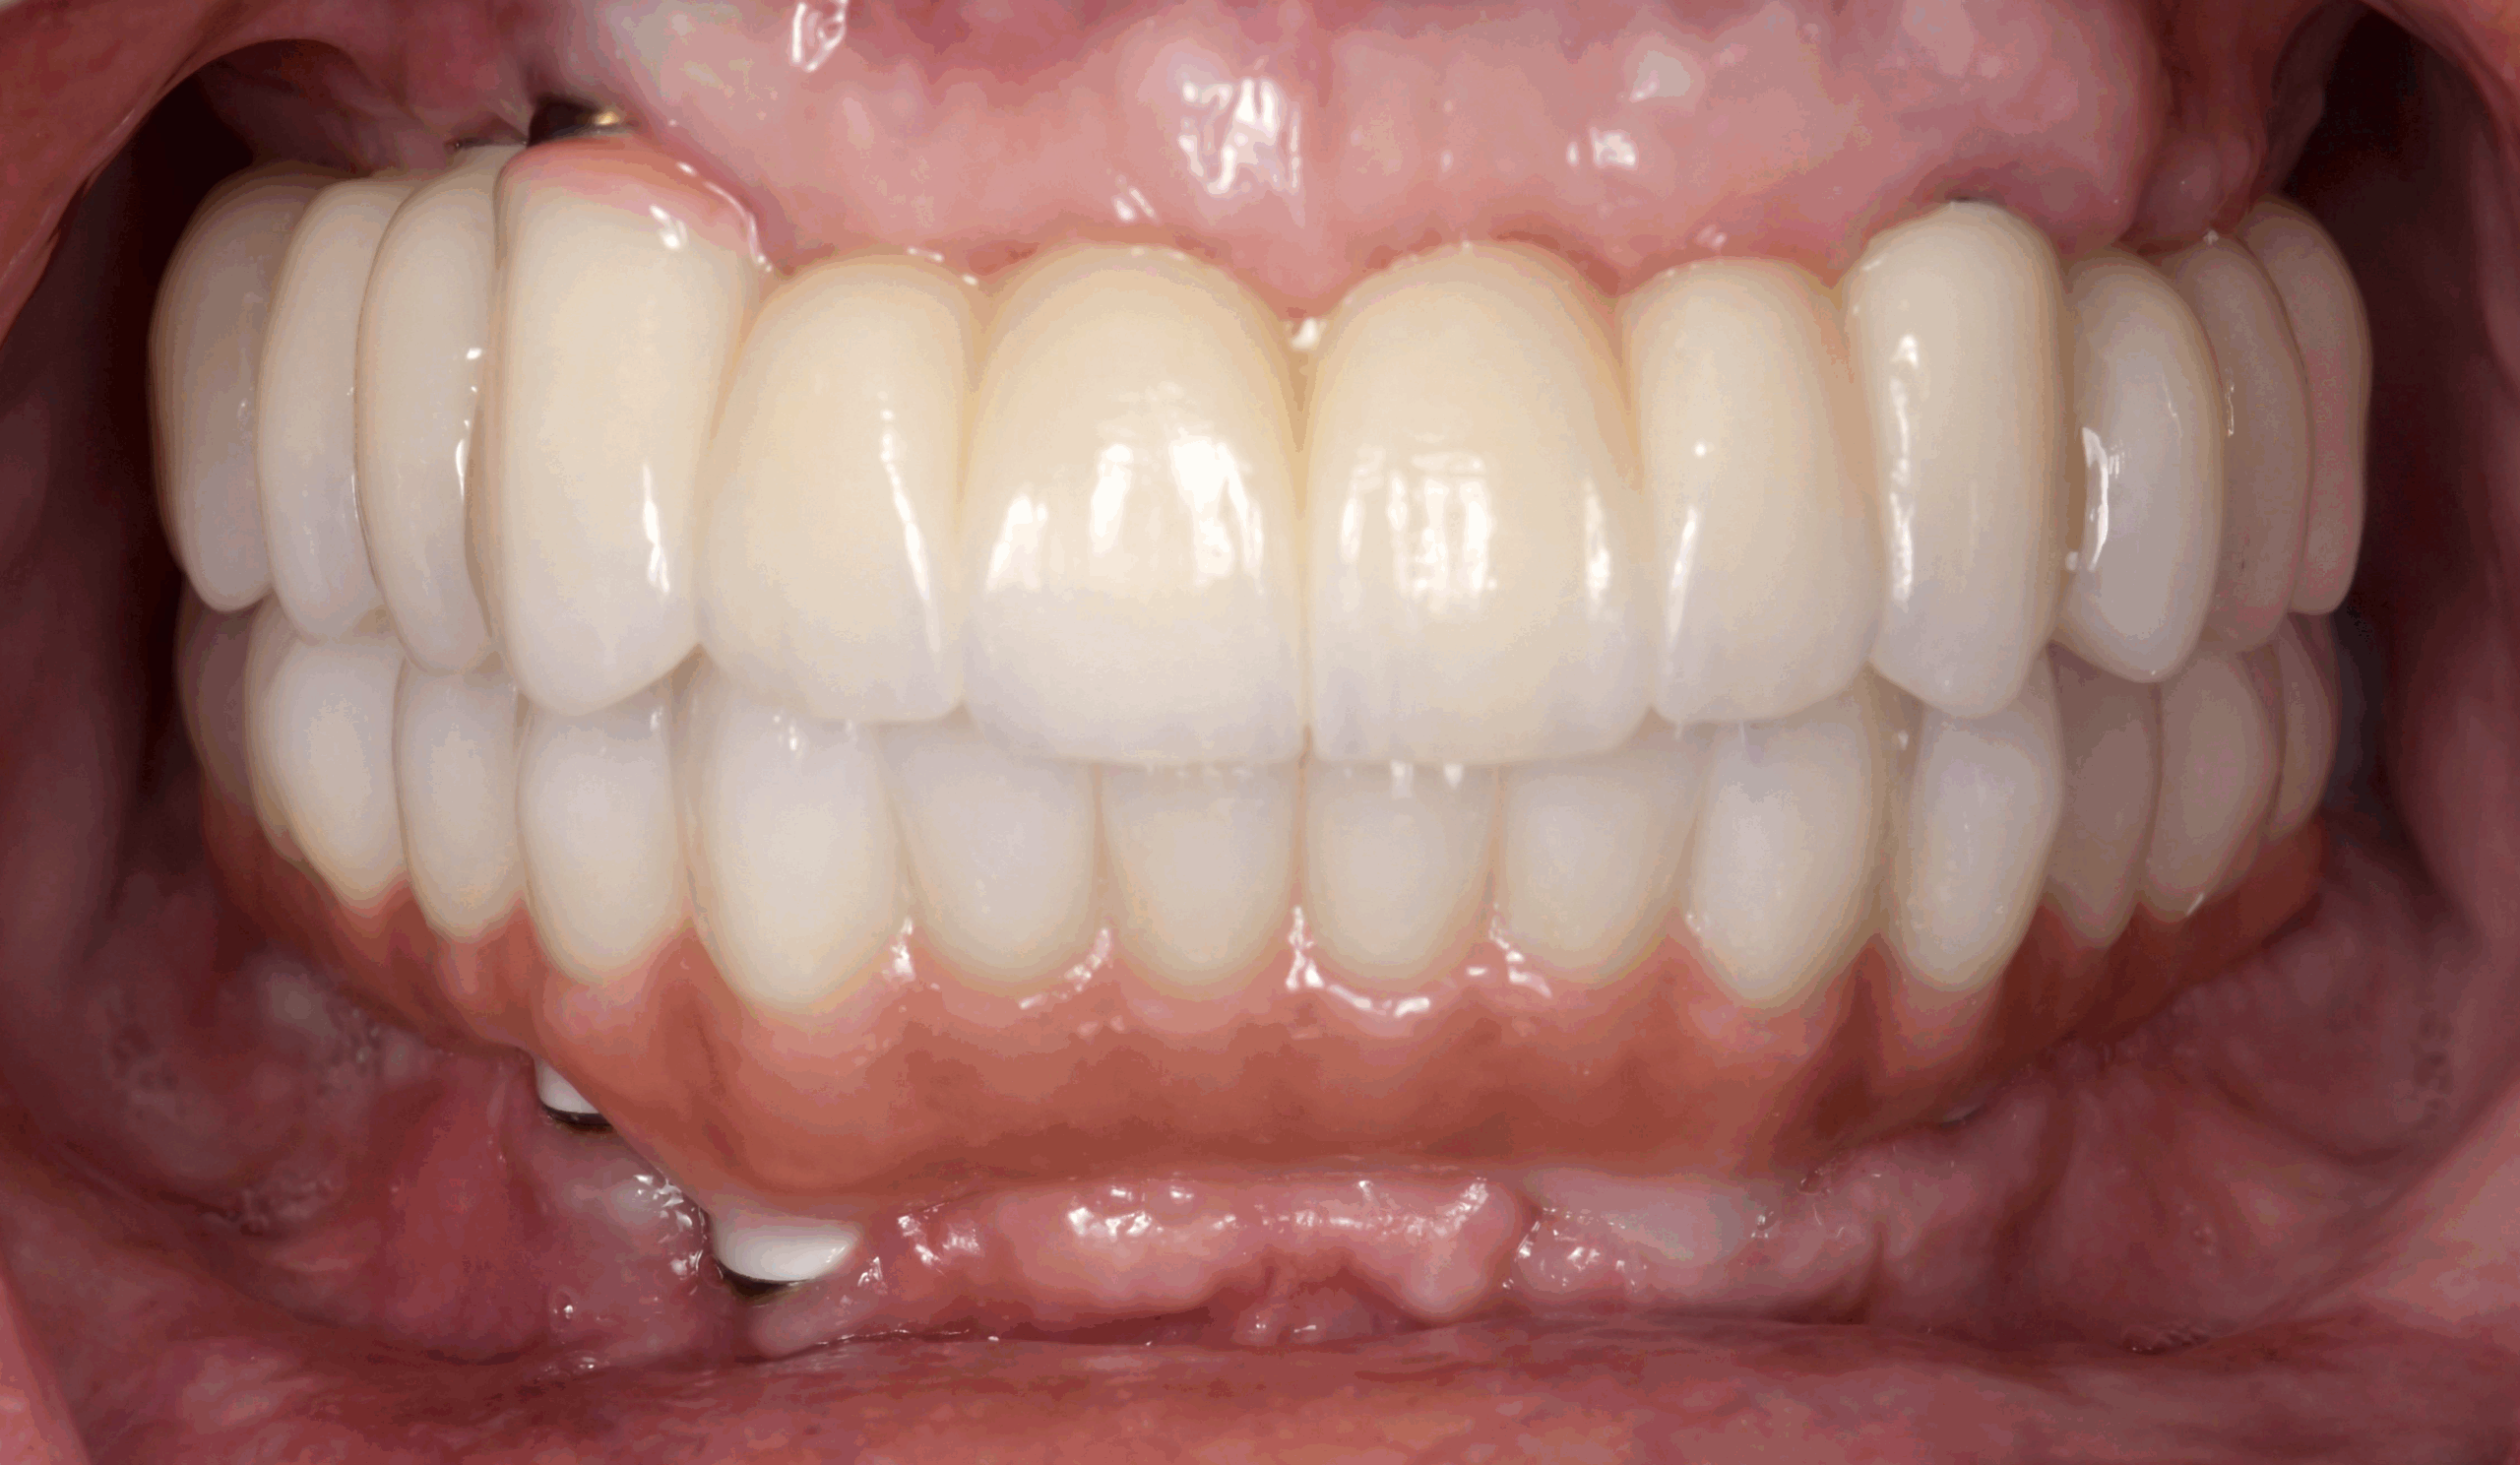

The patient had her implants placed 20 years ago. Four implants, particularly in the maxilla, were not positioned ideally for me to utilize and restore, while the four implants in the mandible were outdated and no longer functional. The patient's primary concern is to restore both function and aesthetics.

All on 6: Facial cut back (PFZ) Zirconia Full arch prosthesis for Maxilla and Mandible Before & After

All on 6 for both arches Implants (#3,4,6,11,13,14,18,21,22,27,28,31)